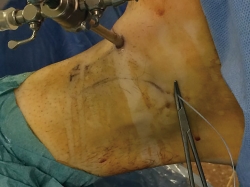

La pierna se coloca en una pernera que sujeta la tibia paralela al suelo y con una posición del tobillo en anteroposterior respecto al suelo, dejando el tobillo libre en el aire, lo que permite una gran zona de trabajo alrededor del mismo (Figura 1).

Figura 1. Colocación de la pierna en la pernera que permite un gran ángulo de trabajo.